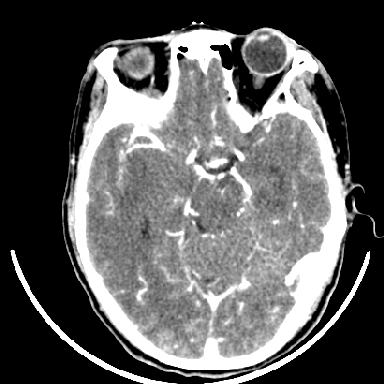

标题: CT6056:脑出血(血管畸形?) [打印本页]

标题: CT6056:脑出血(血管畸形?)

m 40突发头痛左侧偏瘫3小时

考虑高血压性脑出血,依据:

1是高血压性脑出血的好发部位,形态呈肾形,是高血压性脑出血的常见形状

2增强时占位效应加重了,考虑出血还没有停止

3病灶周围水肿不是太厉害,一般肿瘤出血水肿多非常明显

4病灶周围的‘软组织’影没有明显的强化

5至于脑血管畸形引起的出血,暂时没有看到明显的畸形血管影,也不太支持

支持右侧基底节脑出血

右侧基底节区脑出血.

支持右侧基底节区(主要为外囊区)原发性脑出血。

另附部分资料:“血液溢出血管外形成血肿,其内含有大量血红蛋白、血浆白蛋白,球蛋白,因这些蛋白对x线的吸收系数高于脑质,故ct呈现高密度阴影,ct值达40~90h,最初高密度灶呈非均匀一致性,中心密度更高,新鲜出血灶边缘不清。基底节区血肿多为“肾”型,内侧凹陷,外侧膨隆,因外侧裂阻力较小,故向外凸,其它部位血肿多呈尖圆形或不规则形”

术中抽出40ml陈旧血液,血肿底部似见一条索血管影